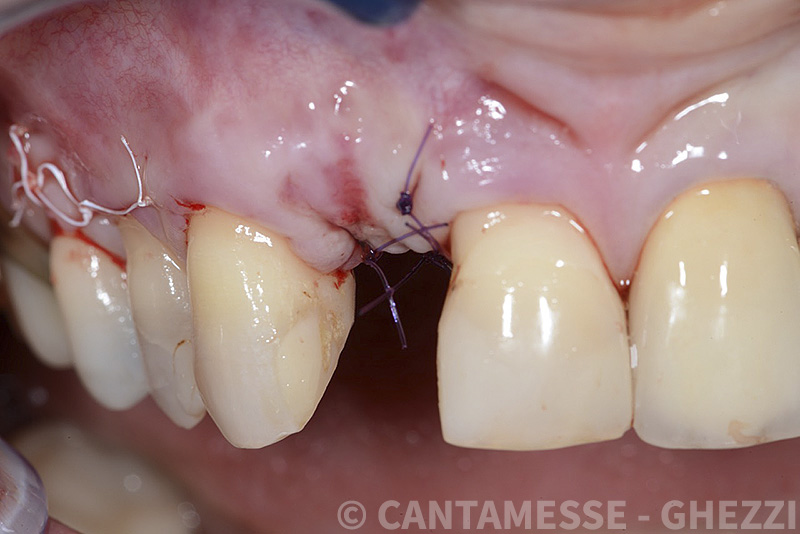

Vengono utilizzati 2 tipi di provvisori: il primo, cementato ai denti vicini, viene utilizzato dal momento dell’estrazione del dente fino ad impianto osteointegrato (circa 6 mesi); il secondo, avvitato direttamente all’impianto, ha una funzione di prova estetica ma soprattutto di guida per la maturazione dei tessuti gengivali peri-implantari portandoli verso la maturazione completa prima di posizionare la corona finale in disilicato di litio.